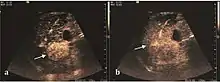

HCC appearance on 2D ultrasound is that of a solid tumor, with imprecise delineation, with heterogeneous structure, uni- or multilocular (encephaloid form). An "infiltrative" type is also described which is difficult to discriminate from liver nodular reconstruction in cirrhosis. Typically HCC invades liver vessels, primarily the portal veins but also the hepatic veins . Doppler examination detects a high speed arterial flow and low impedance index (correlated with described changes in tumor angiogenesis). The spatial distribution of the vessels is irregular, disordered. CEUS examination shows hyperenhancement of the lesion during the arterial phase. During the portal venous phase there is a specific "wash out" of ultrasound contrast agent (UCA) and the tumor appears hypoechoic during the late phase. Poorly differentiated tumors may have a stronger wash out leading to an isoechoic appearance to the liver parenchyma during portal venous phase. This appearance was found in approx. 30% of cases. The described changes have diagnostic value in liver nodules larger than 2 cm.

On CEUS examination, early HCC has an iso- or hypervascular appearance during the arterial phase followed by wash out during portal venous and late phase. There are studies showing that the wash out process is directly correlated with the size and features of neoplastic circulatory bed. Thus, highly differentiated HCC illustrates the phenomenon of late or even very late "wash out" while poorly differentiated HCC has an accelerated wash out at the end of arterial phase. It is therefore mandatory to analyze all these three phases of CEUS examination for a proper characterization of liver nodules. Tumor wash out at the end of the arterial phase allows the HCC diagnosis with a predictability of 89.5%. Some authors consider that early pronounced contrast enhancement of a nodule within 1–2 cm developed on a cirrhotic liver is sufficient for HCC diagnosis. These results prove that for a correct characterization of the lesions it is necessary to extend the examination time to 5 minutes or even longer.